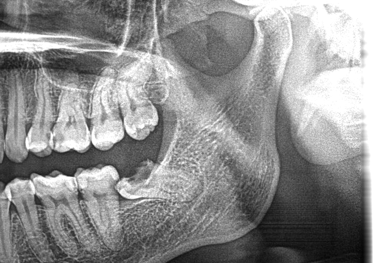

Jaw Cysts & Tumours

Expert surgical care for jaw cysts and tumours, with a strong emphasis on precision, safety, and comprehensive treatment planning.